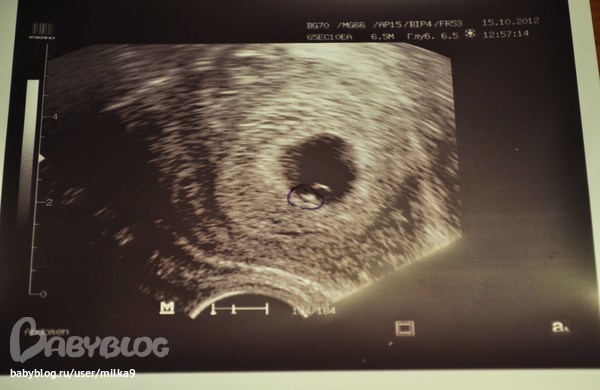

15.10.12 сходила на узи.Сама, платно, т.к. в прошлй раз нашу лялю не увидели, а видно было только плодное яйцо, хотя на этом сроке обычно видно.

В этот раз нашу крошку было уже видно)) я так была счастлива) И сердцебиение уловили) Правда срок мне опять поставили 5-6 неделек. Масенькие мы))

А вот и мини-мы

6 неделек, 5 дней))

То, что обведено ручкой - это ляля)) а сверху - это желточный мешочек ( будущая плацента)